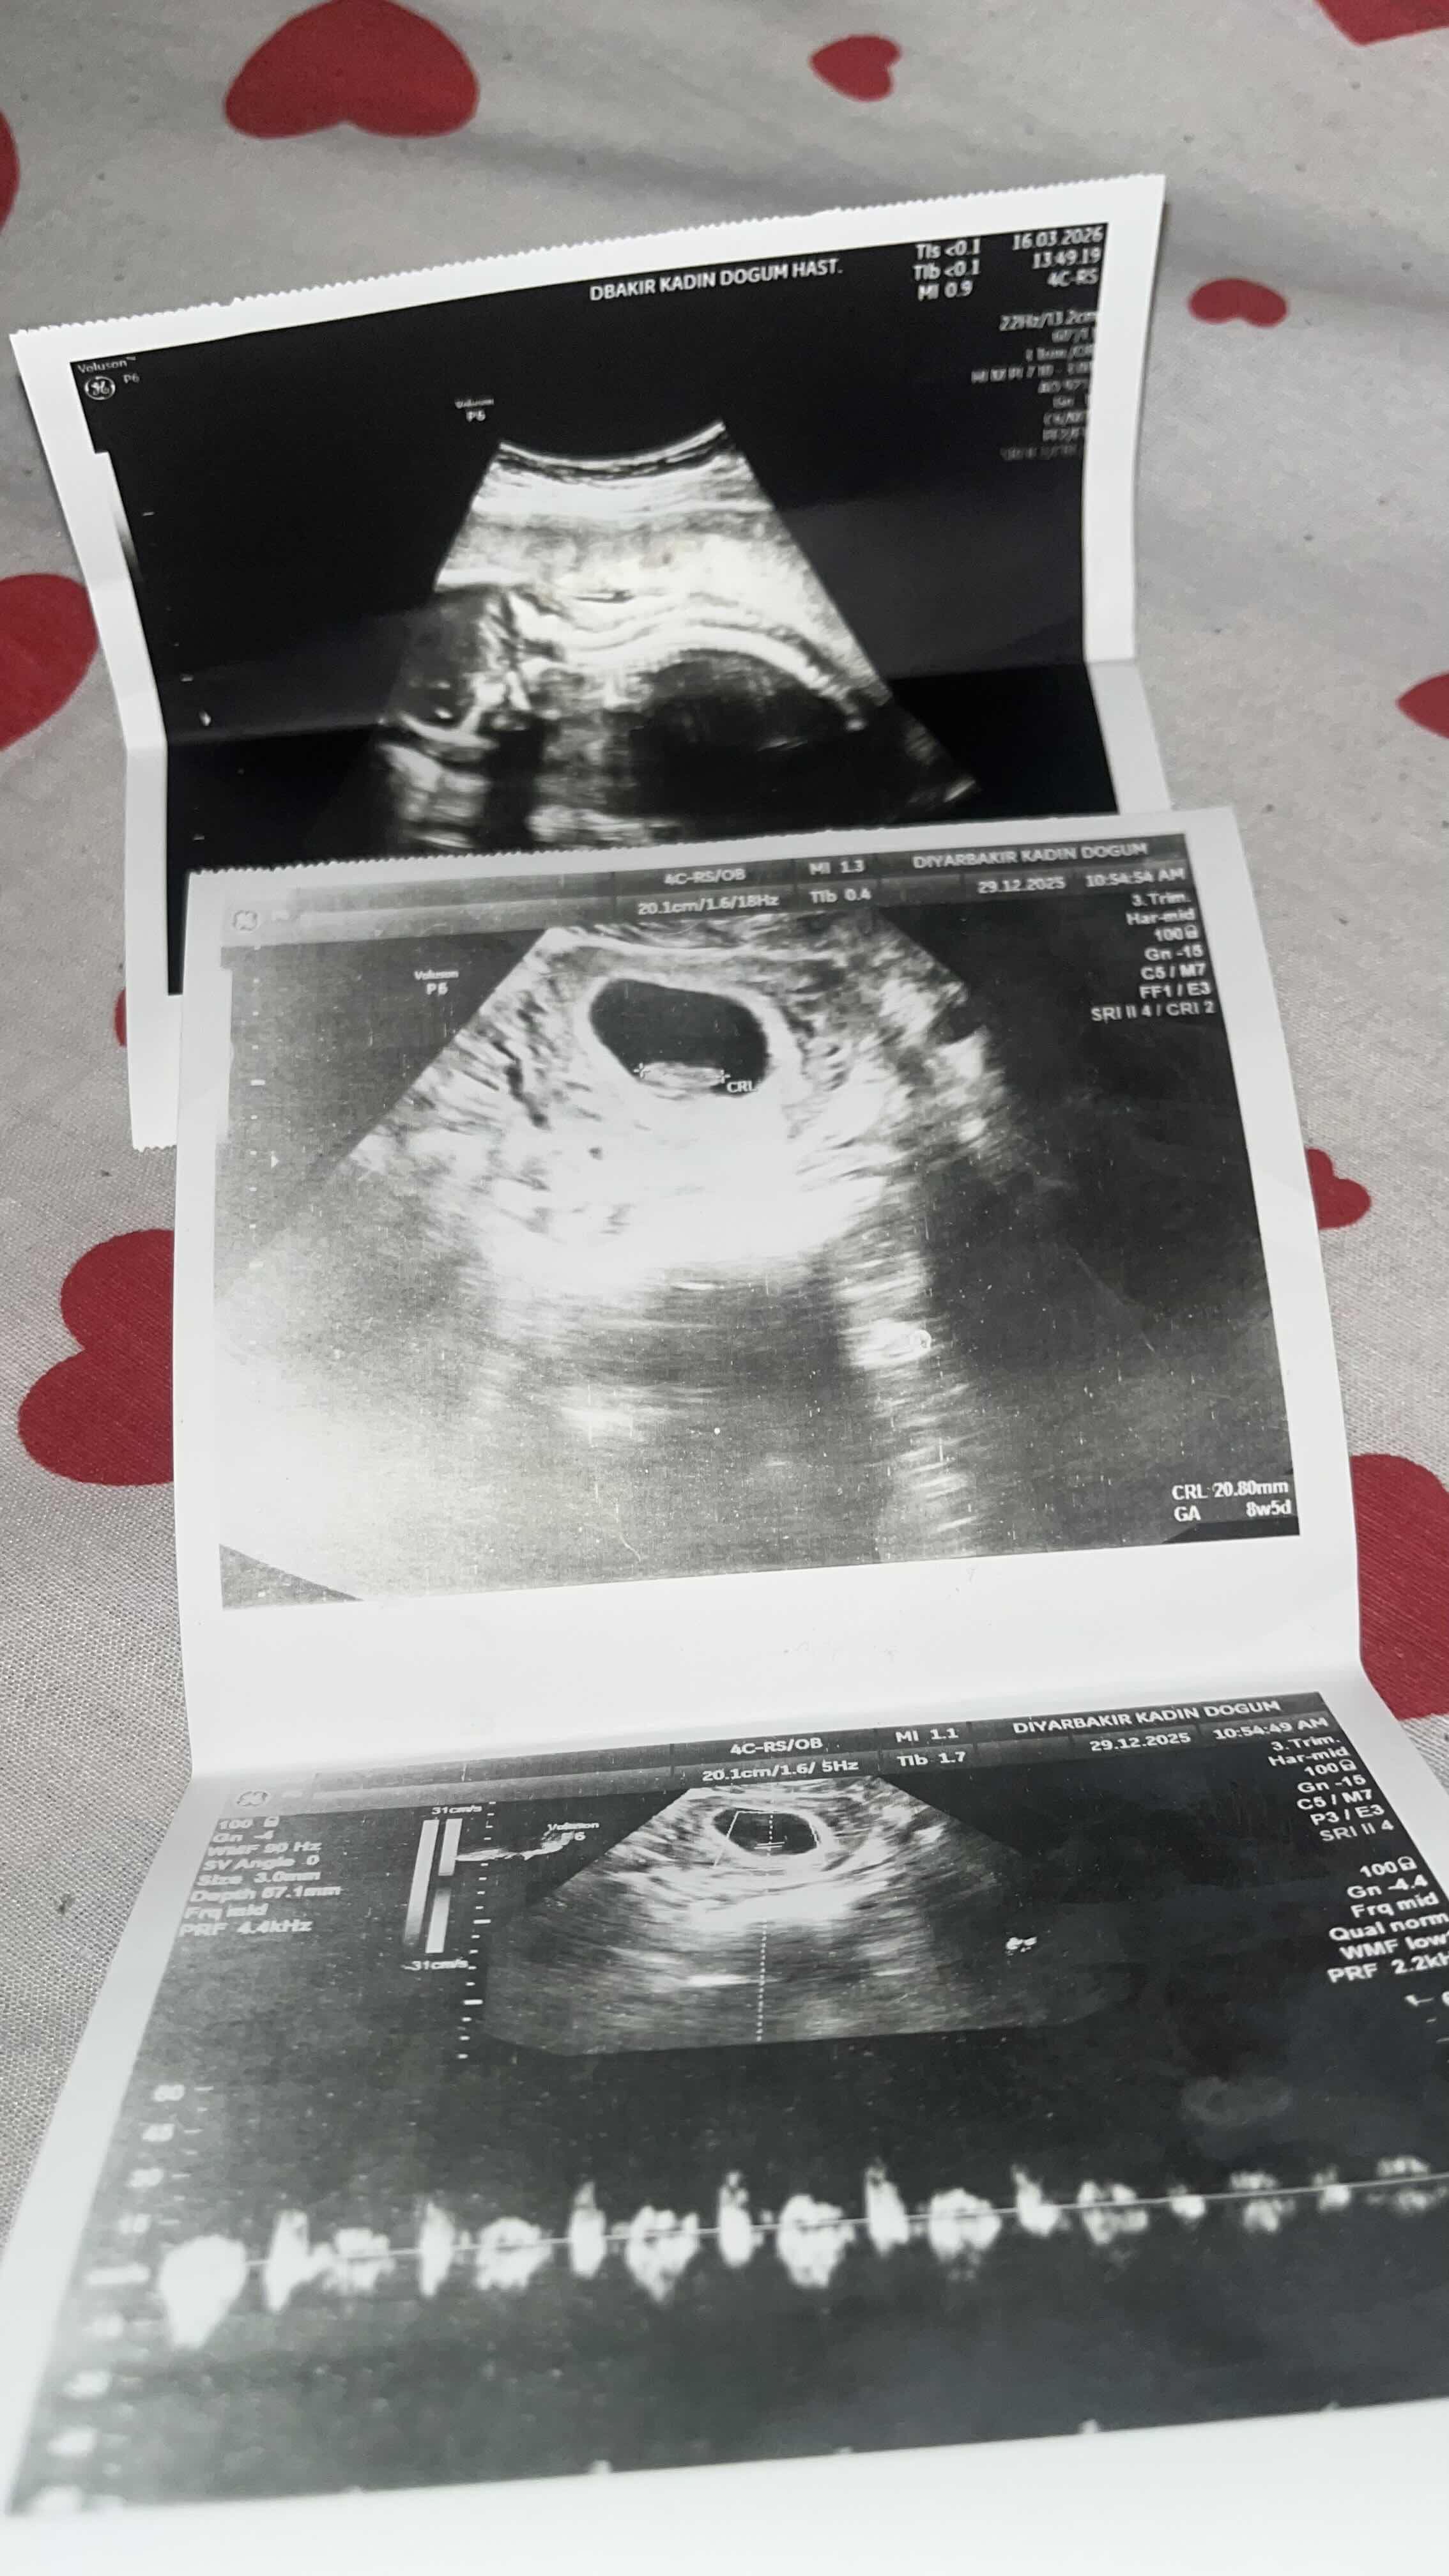

السلام عليكم انا حامل في الاسبوع ال 19 ولدي اعراض الحمل بولد رحت دكتوره قالتلي الجنين مقلوب واريد الان معرفه جنس الجنين هل انثى ام ذكر

هذا الجنين صغير وليس الاسبوع ١٩...!!! 0 2026-03-18T22:13:10+00:00 2026-03-18T22:13:10+00:00

هذا الجنين صغير وليس الاسبوع ١٩...!!!